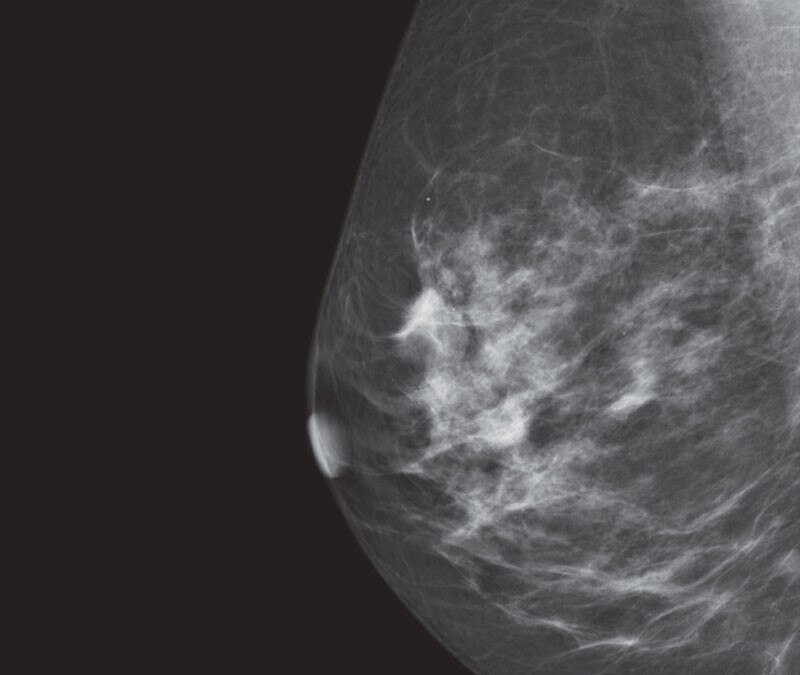

Deep learning in 3D breast image reconstruction

Pristina Recon DL

Pristina Recon DL* pushes 3D mammography past limits, delivering images with greater purity. A paradigm shift born from GE HealthCare’s pioneering AIR™ Recon DL, it operates a dual DL technology that reveals fine details, minimizing artifacts and perceived noise1,2